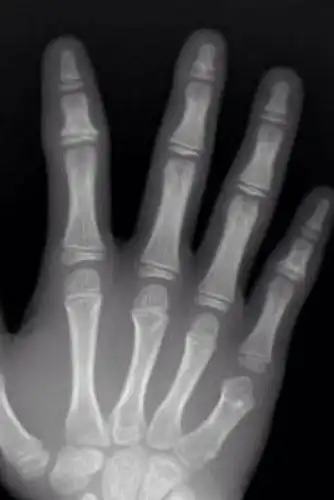

今天去拍了手骨的片子看看骨骺线闭合没,还能长多高,懂的人给我看看吧

骨骺线完全闭合的20岁成年人骨龄片(左)骨骺线未闭合的7岁儿童骨龄片

骨骺线闭没闭合对比图